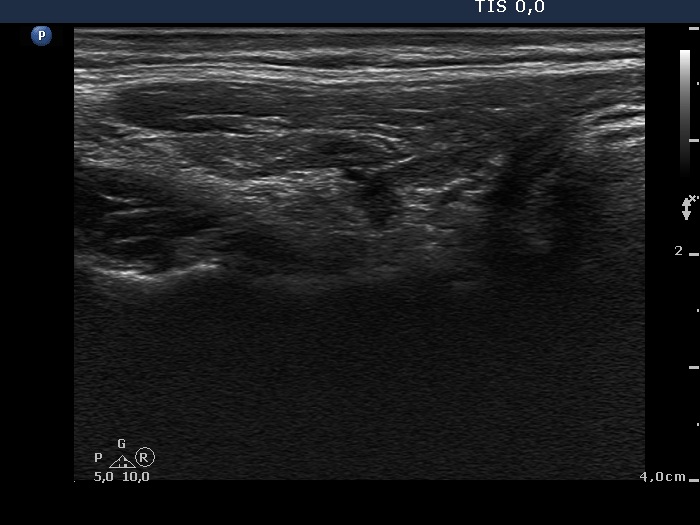

One year after radioiodine therapy (third row):

Clinical presentation: the patient had no complaints.

Palpation: the thyroid could not be palpated.

Functional state: mild hypothyroidism on daily 112.5 microgram levo-tiroxine (TSH-level 5.11 mIU/L).

Ultrasonography: the thyroids were hypoechogenic and presented extensive fibrosis. The size of the lobes decreased significantly. The thyroid presented no and decreased vascularization, right and left lobe, respectively.

Suggestion to increase the dose of levo-tiroxine to daily 125 microgram.